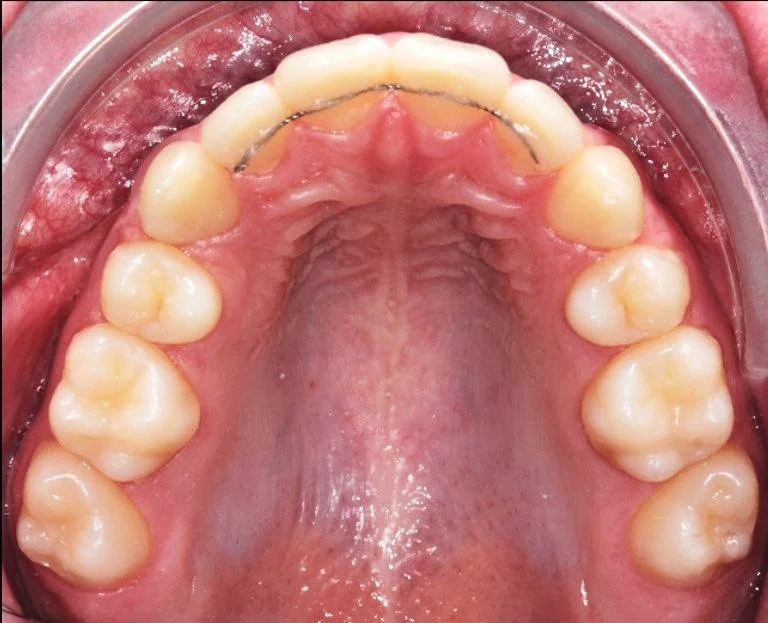

ORTODONZIA INTERCETTIVA + ALLINEAMENTO

AFTER

Caso di una paziente con morso aperto iniziale e palato stretto, trattato in giovane età con terapia intercettiva mediante espansione rapida del palato. Successivamente, in adolescenza, è stata sottoposta a trattamento ortodontico fisso in dentatura permanente.